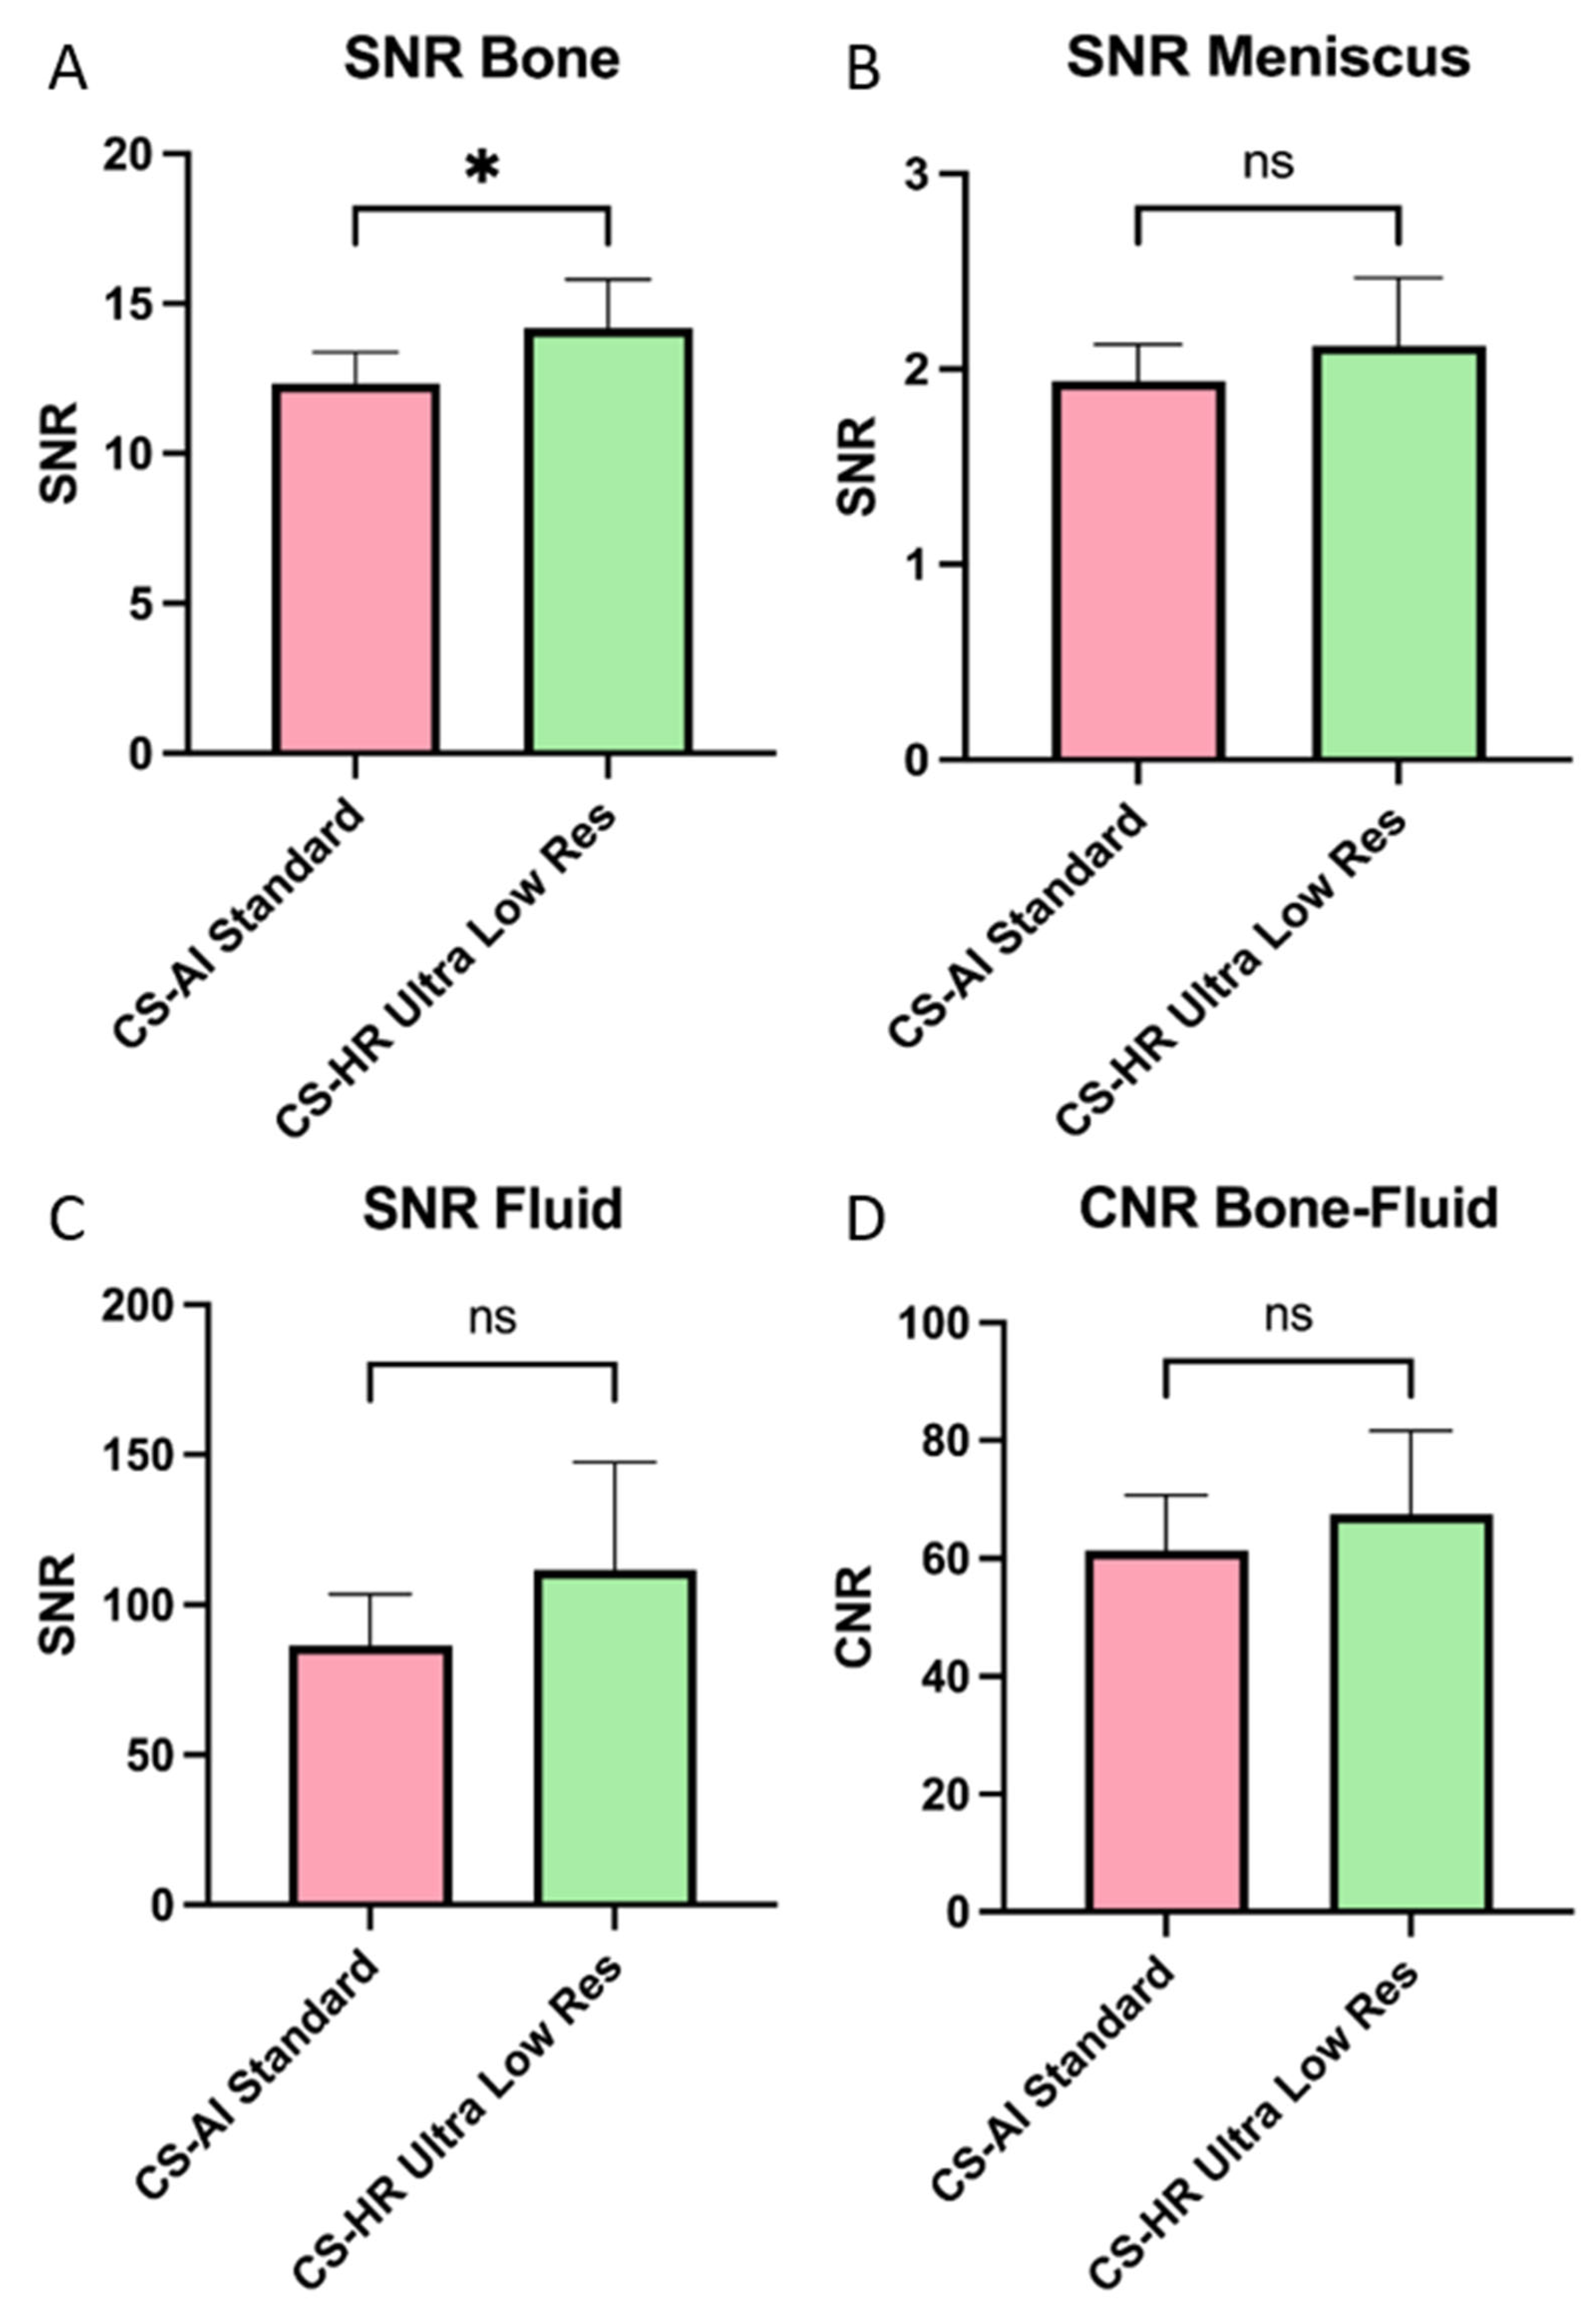

3.4. Objective Image Analysis